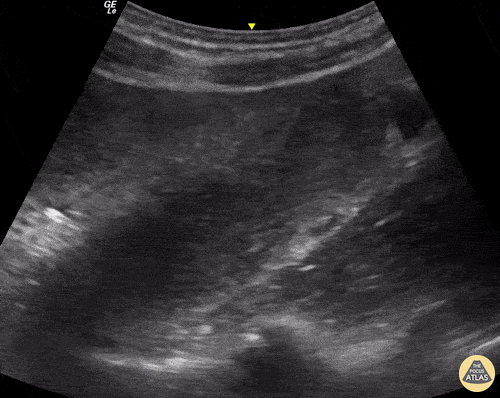

This 70-year-old male presented to our ED reporting abdominal pain and vomiting with associated absence of flatus / bowel movements. Seen here is his LUQ abdominal view using the curvilinear probe that reveals a dilated loop of bowel. The image is further characterized by increased peristalsis (the "To and Fro" sign) as well as the presence of free fluid adjacent to the dilated bowel loop in the shape of a triangle (known as the "Tanga Sign"). This case highlights how bedside ultrasound can be a powerful tool to enable prompt diagnosis and treatment of bowel obstruction. Renato Tambelli, Emergency Physician Hospital das Clínicas de Marília, Brazil. @R_Tambelli // @JediPocus